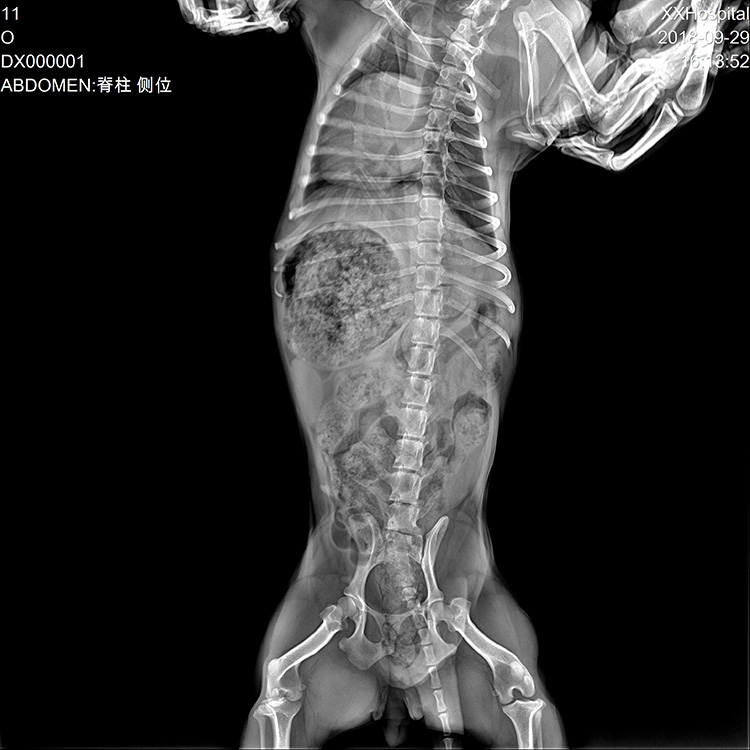

The MSLCV08 is a 17X17 box-type wireless portable flat panel detector designed for human digital radiography.

- 1. Fast workflow

2. More image details

3. Excellent image quality